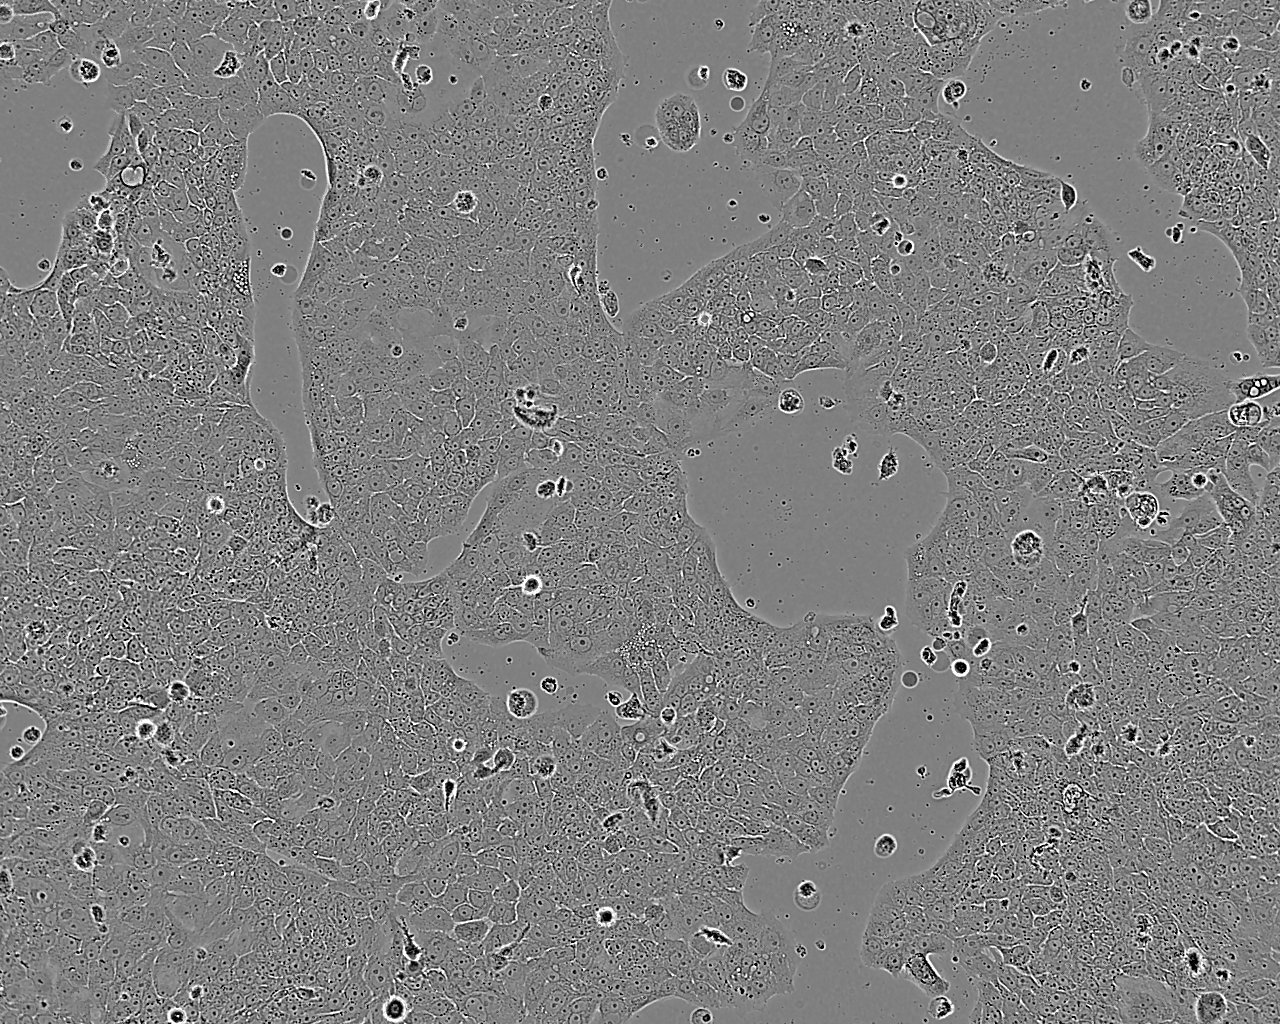

SW837 人直肠腺癌细胞

形态特征 上皮细胞样

生长特征 贴壁